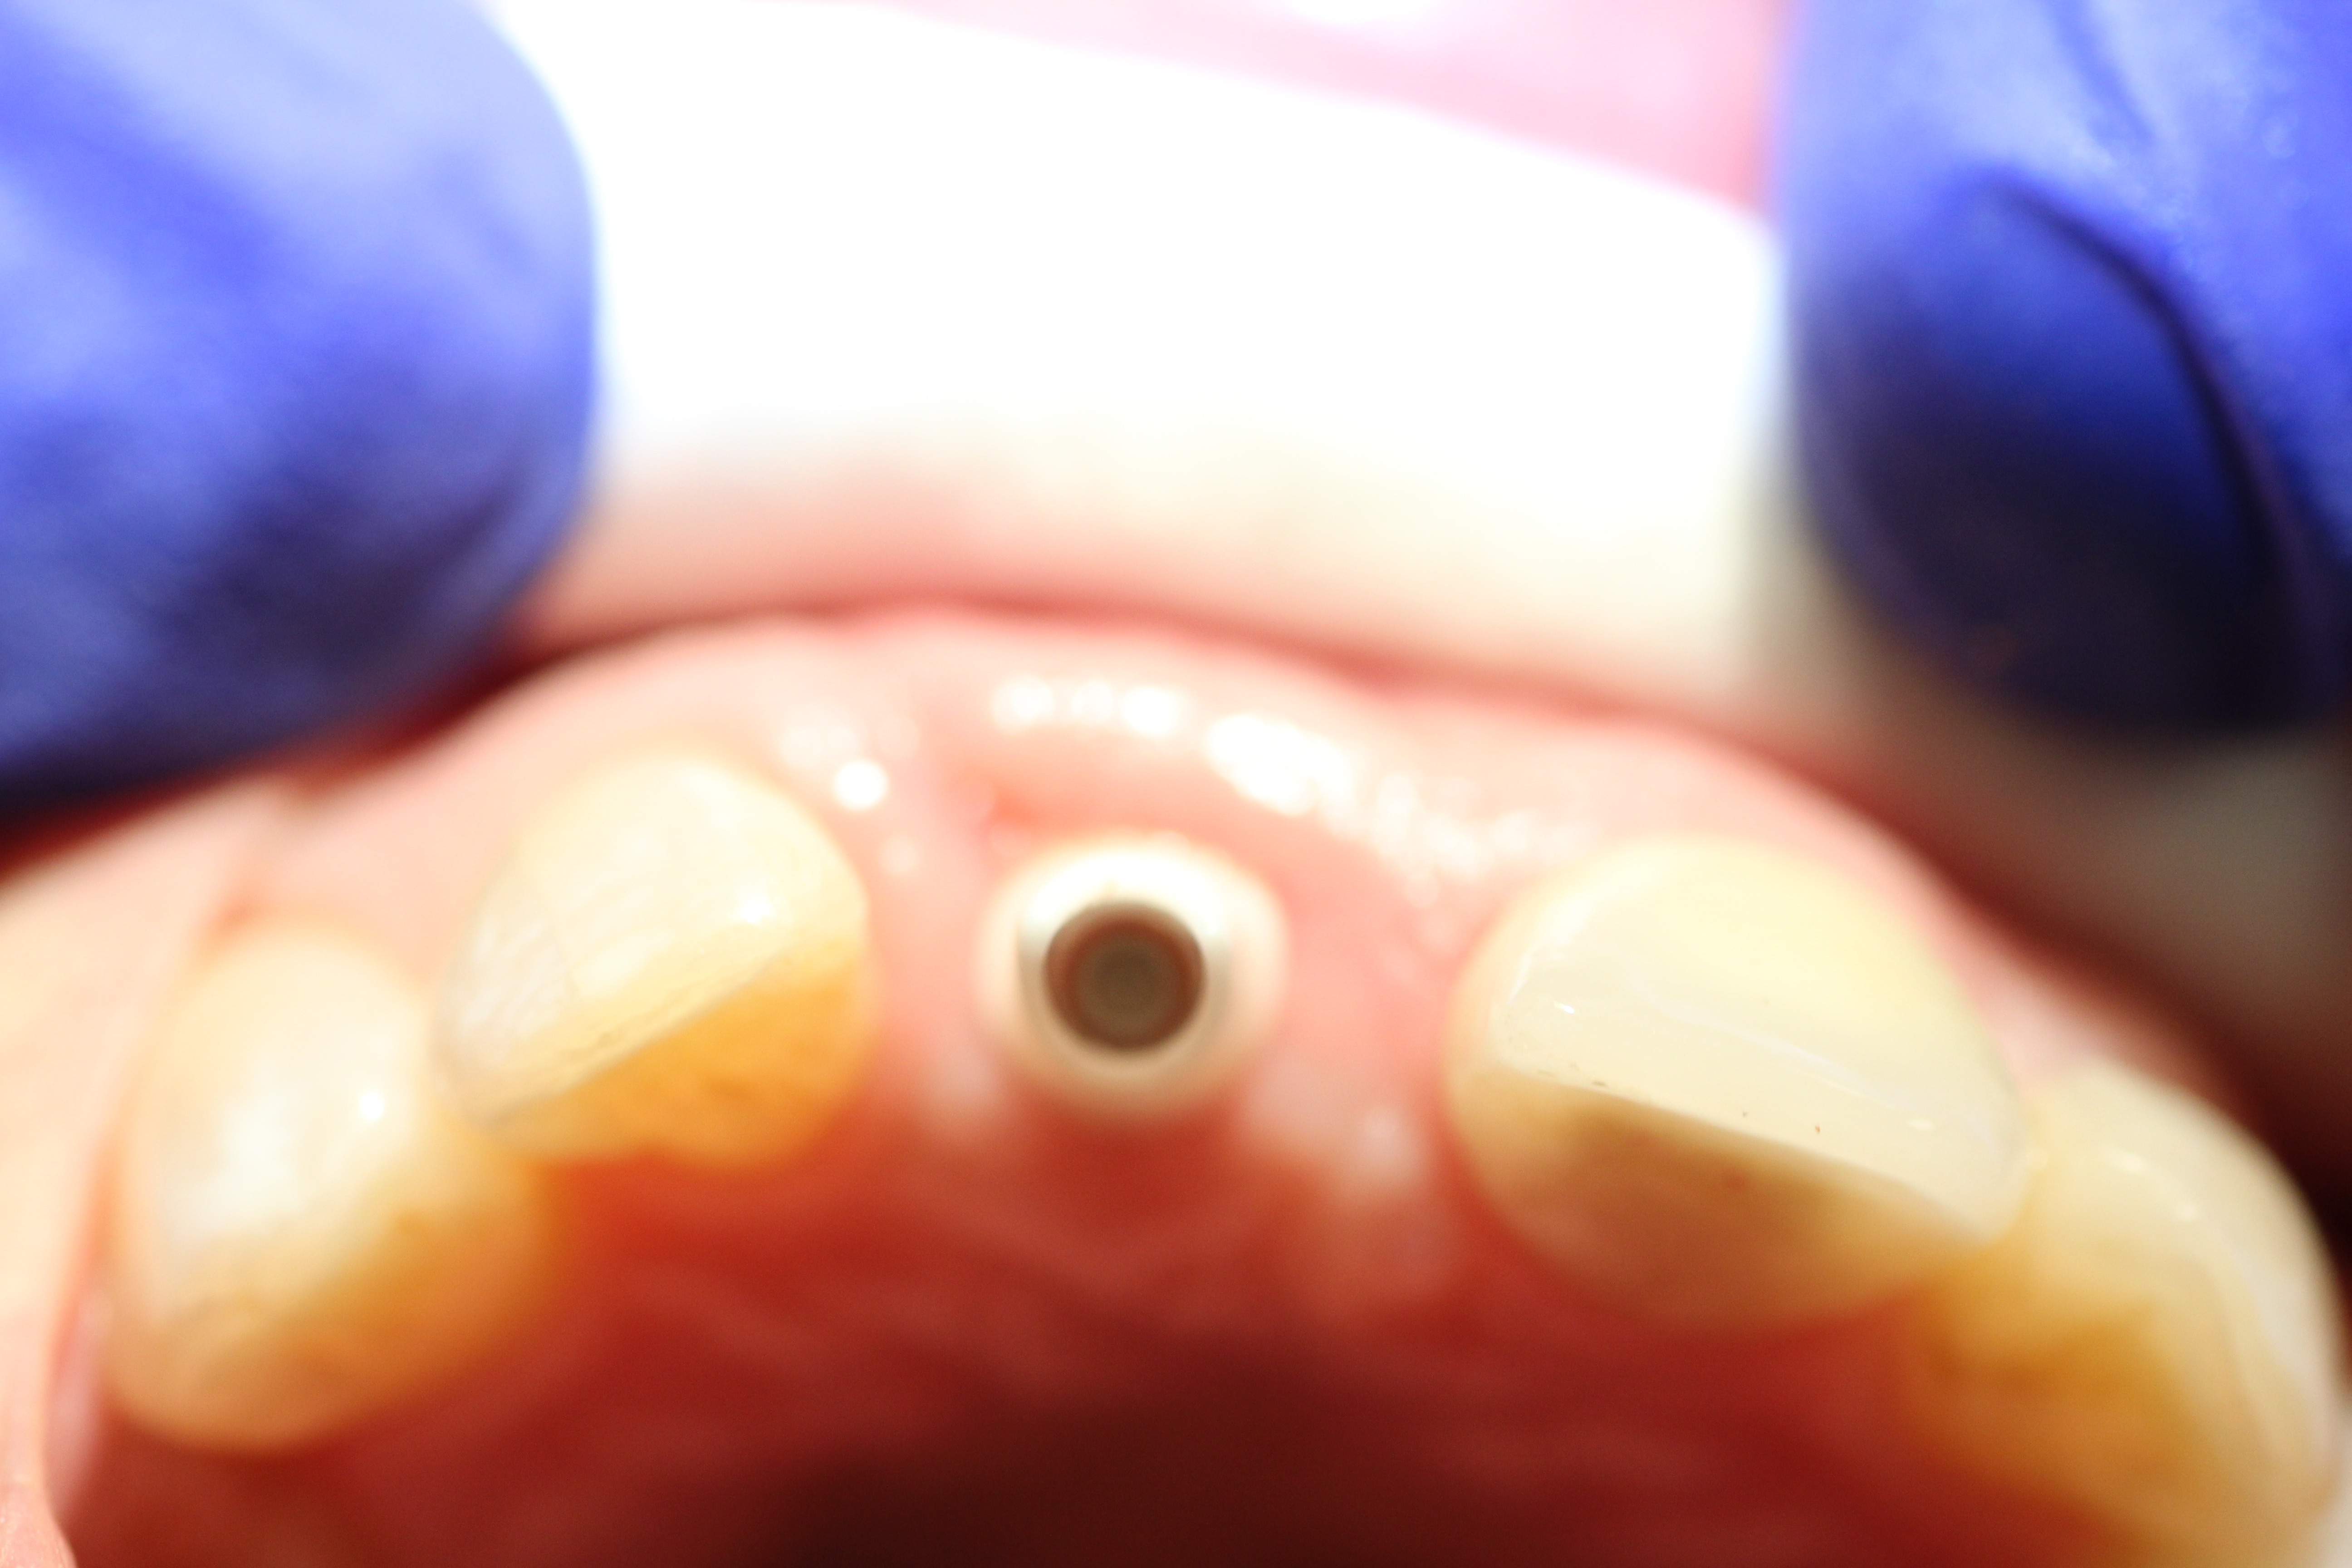

Case #1

Implant placement with immediate provisionalization in an aesthetic zone.

- Implant being placed.

- Implant being sutured while the temporary crown is being made.

- Temporary crown made.

- Temporary crown in place.